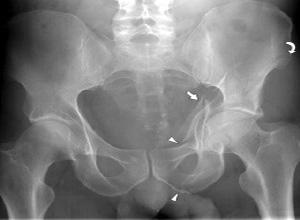

髋臼骨折大多数是由股骨头受到外界暴力传导引起的,常会遗留以下三种并发症:

1、异位骨化

异位骨化是髋臼骨折患者最主要的并发症,是导致手术治疗预后不良的主要原因,有1/3的患者需要再次手术治疗才能解除。异位骨化发生的原因与损伤严重程度、手术位置、骨膜剥离程度、截骨术的应用等因素有关。

3、创伤后关节炎

创伤后关节炎是髋臼骨折的远期并发症,多见于髋臼上臂骨折和髋关节后脱位。其发生原因与股骨头承重面骨折、永久性关节半脱位、关节面不对称等因素有关,手术治疗时尽量恢复良好的解剖复位,尤其是髋臼负重面的解剖复位可以有效的降低创伤后关节炎的发生率。